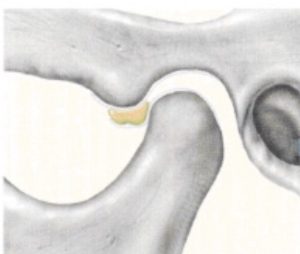

顎の病気で最も多いのは関節内にある関節円板と言うクッションが前方にずれることで起きるカクンカクン言う音が出る状態があります。

顎関節の内部には関節円板があり、これが軸と軸受けとの間にあります。下顎頭は口を開けるときに前方に移動します。その時関節円板は一緒に移動して仮の軸受となります。

関節円板が前方にズレていて、変形してる状態。